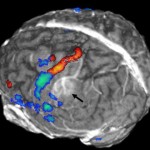

I ricercatori della Newcastle University, guidati dal dottor Akash Sinha del Newcastle upon Tyne Hospitals NHS Foundation Trust, hanno indagato i tempi di recupero di fosfocreatina in pazienti con deficit di vitamina D. Hanno utilizzato un metodo non invasivo di scansione a risonanza magnetica per misurare la dinamica della fosfocreatina in risposta all’esercizio fisico nei muscoli del polpaccio, di 12 pazienti con grave carenza di vitamina D prima e dopo il trattamento con vitamina D. Questa è la prima volta che viene condotto uno studio di questo tipo .

Il team ha scoperto che il recupero di fosfocreatina è migliorato significativamente dopo che i pazienti hanno assunto una dose fissa di vitamina D per via orale per 10-12 settimane (in media il tempo di recupero di fosfocreatina mezzo diminuito da 34.4sec a 27.8sec, p <0,001). Tutti i pazienti hanno riferito un miglioramento dei sintomi di stanchezza con supplementazione seguente. In uno studio parallelo, il gruppo ha dimostrato che bassi livelli di vitamina D erano associati a ridotta funzionalità mitocondriale (r = -0,41, p = 0,009).